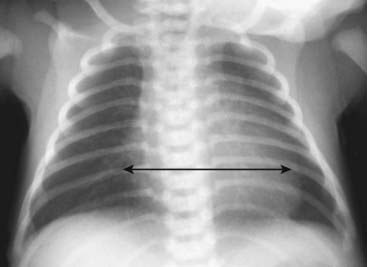

Recognizing Cardiomegaly in Infants

image Although this chapter focuses primarily on adult cardiac disease, in newborns and infants it is important to remember that the heart will normally appear larger relative to the size of the thorax than it does in adults. Whereas a cardiothoracic ratio greater than 50% is considered abnormal in adults, the cardiothoracic ratio may reach up to 65% in infants and still be normal because newborns cannot take as deep an inspiration as adults can and the relative proportions in the size of their abdomen to chest are not the same as for adults (Fig. 9-4).

image Any assessment of cardiac enlargement in an infant should take into account other factors such as the appearance of the pulmonary vasculature and any associated clinical signs or symptoms (e.g., a murmur, tachycardia, or cyanosis).

Figure 9-4 Normal infant chest.

In the normal infant, the cardiothoracic ratio may be as large as 65% (compared to 50% in adults) (double arrow). Any assessment of cardiac enlargement in an infant should also take into account other factors such as the appearance of the pulmonary vasculature and any associated clinical signs or symptoms (such as a murmur, tachycardia, or cyanosis).